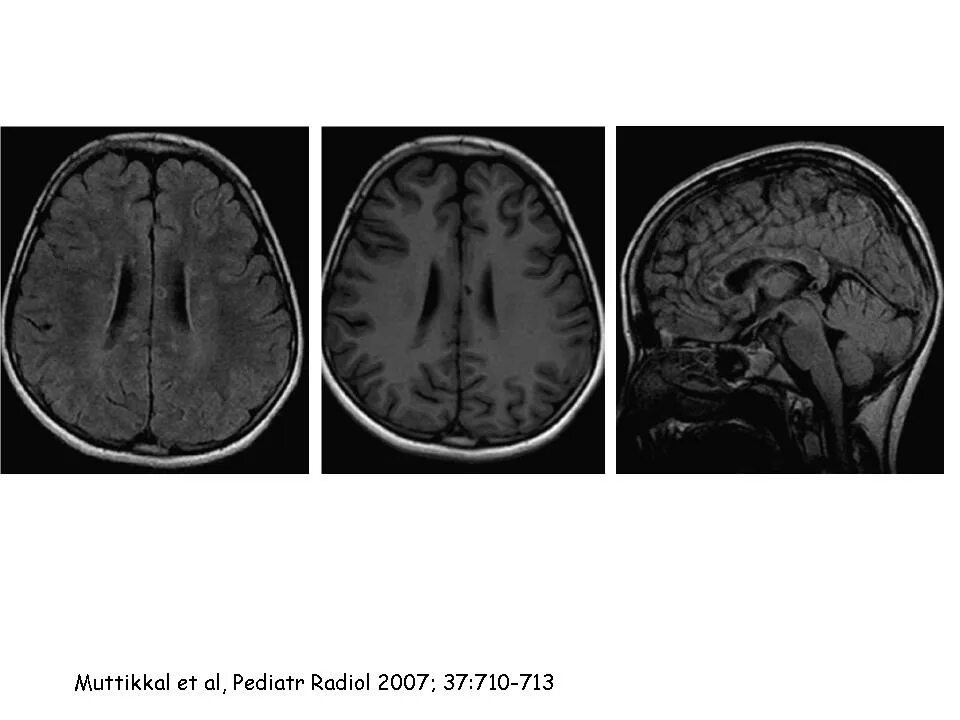

Диффузные изменения вещества головного мозга